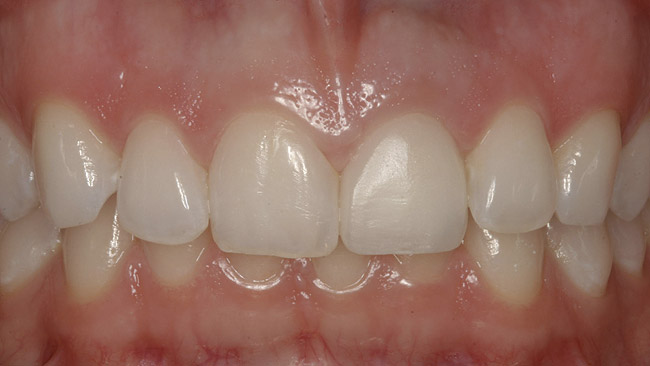

Figure 1  Initial presentation with yellow, poorly color-matched restored mandibular anterior teeth.

Figure 1

Figure 8  Full smile—finished feldspathic crowns on teeth Nos. 22, 23, 27, and 28; implant crowns in sites 24 through 26; esthetic harmonization with opposing dentition.

Figure 8

This patient faced a unique situation, perhaps not previously reported: retaining a healthy mandibular lateral incisor knowing this would create an esthetic compromise. Indeed, while the discrepancy in gingival-margin height is noticeable in retracted view (Figure 7), it does not show in full smile (Figure 8).